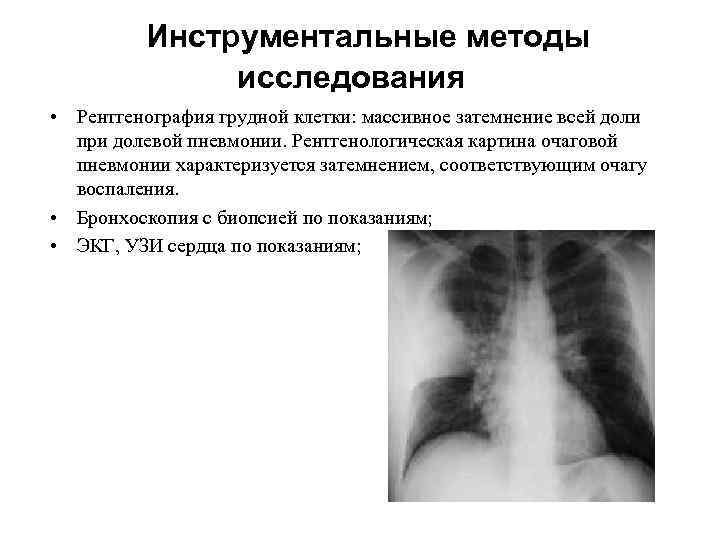

Инструментальные методы исследования • Рентгенография грудной клетки: массивное затемнение всей доли при долевой пневмонии. Рентгенологическая картина очаговой пневмонии характеризуется затемнением, соответствующим очагу воспаления. • Бронхоскопия с биопсией по показаниям; • ЭКГ, УЗИ сердца по показаниям;